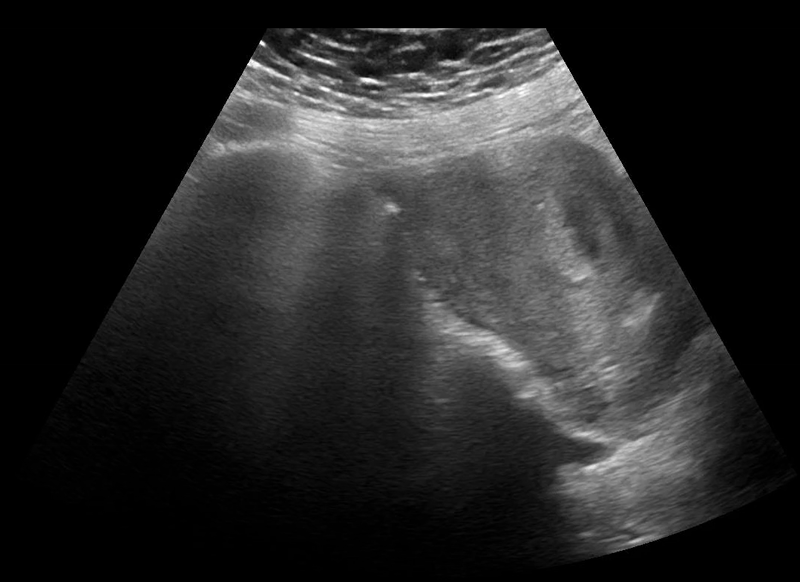

POCUS transabdominal revealed no free fluid in hepatorenal space (image 1), and the uterus without an intrauterine pregnancy (image 2) but with pelvic free fluid (image 3). The left adnexa revealed a gestational sac with a yolk sac (image 4), diagnostic for an ectopic gestation.

Image 4: Now focusing on the left adnexa, there is a clear ectopic pregnancy (an extrauterine gestational sac with yolk sac within).